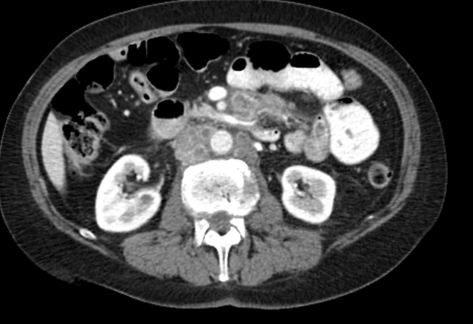

The visceral and parietal surfaces of the peritoneum touch each other, but never fuse. Between them lies a __potential space__ containing a thin film of proteinaceous fluid lubricating the two surfaces. Every day during the fall of 1981 I asked my professor to explain __potential space.__ "Imagine the inside of a pillow case without the pillow," he said. The pillow case is flattened and laid over the abdominal organs, and then pushed into the rounded corners between liver, spleen, pancreas, bowel, fat, and blood vessels. The outside of the pillow case is fused to the connective tissue at the back of the abdomen, the organs, including the entire length of the small and large bowel, and the abdominal wall. Inside the pillow case is the peritoneal cavity. The abdominal organs reside inside the abdomen, but outside the peritoneal cavity. One of these pillow cases also covers each lung and the heart, creating the pleural spaces and the pericardium.

In health, the peritoneal cavity is as described above. With ovarian cancer it may be filled with cancer cells suspended in thick amber, bloody fluid. In liver disease or heart failure it may contain ascites–thin fluid that leaks out of the blood vessels serving the bowel. If this all makes perfect sense to you and you are not a physician, then __wow__, you are smarter than I am–or maybe it is because I explained it to you so well! I am no dummy. I was runner-up for the anatomy prize for first year medical students at Duke in 1981.